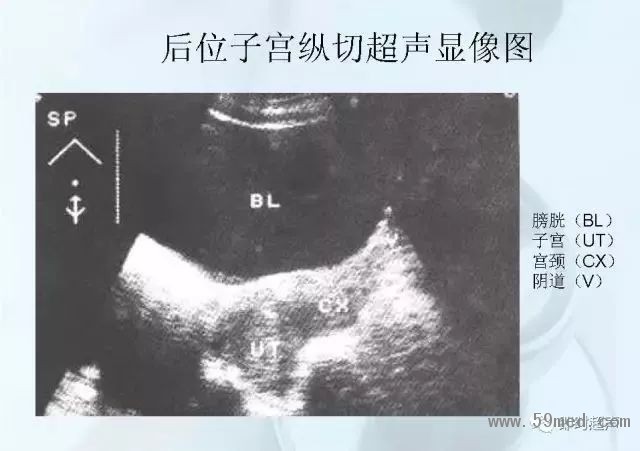

新聞中心 收藏!正常B超解剖圖譜,超實用!